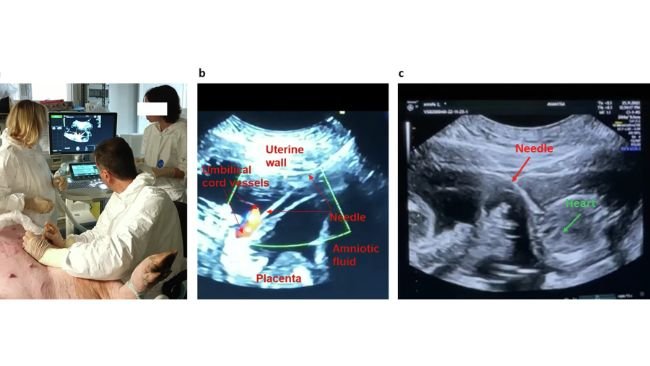

Inoculazione di AAV9-GFP ai feti guidata da ecografia transaddominale della scrofa gravida: un modello traslazionale e minimamente invasivo per la terapia genica fetale in utero

Quando i suini sono al servizio della salute umana. Lo studio realizzato presso l'Istituto Avantea di Cremona è stato pubblicato su Nature...